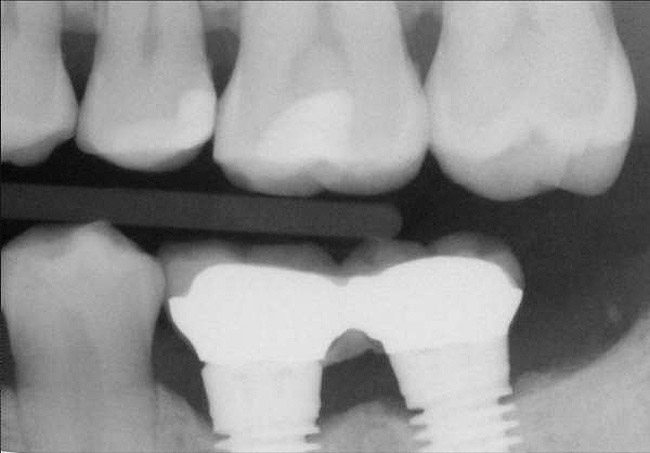

Figure 13  Radiograph depicting the necessity of horizontal placement parameters to prevent vertical defects from becoming horizontal defects.

Figure 13

Horzontal Components of Implant Placement

The horizontal aspect of implant spacing is critical to avoid bone loss on adjacent teeth or implants. Single-tooth implants should be placed 1.5 mm to 2 mm from the adjacent teeth,19,20 and implants should have at least 3 mm of space between them21 (Figure 12). By keeping a minimum 1.5-mm distance from the adjacent tooth and a minimum distance of 3 mm between adjacent implants, angular defects resulting from crestal bone remodeling can be kept from becoming horizontal defects19-22 (Figure 13). This distance allows the bone on the adjacent tooth to stay at its current level. Conversely, if bone loss on the adjacent tooth or implant occurs, the bone loss will not affect the adjacent tooth or implant. This is especially critical in the anterior regions of the mouth where papilla height is more important for an esthetic result.23-27